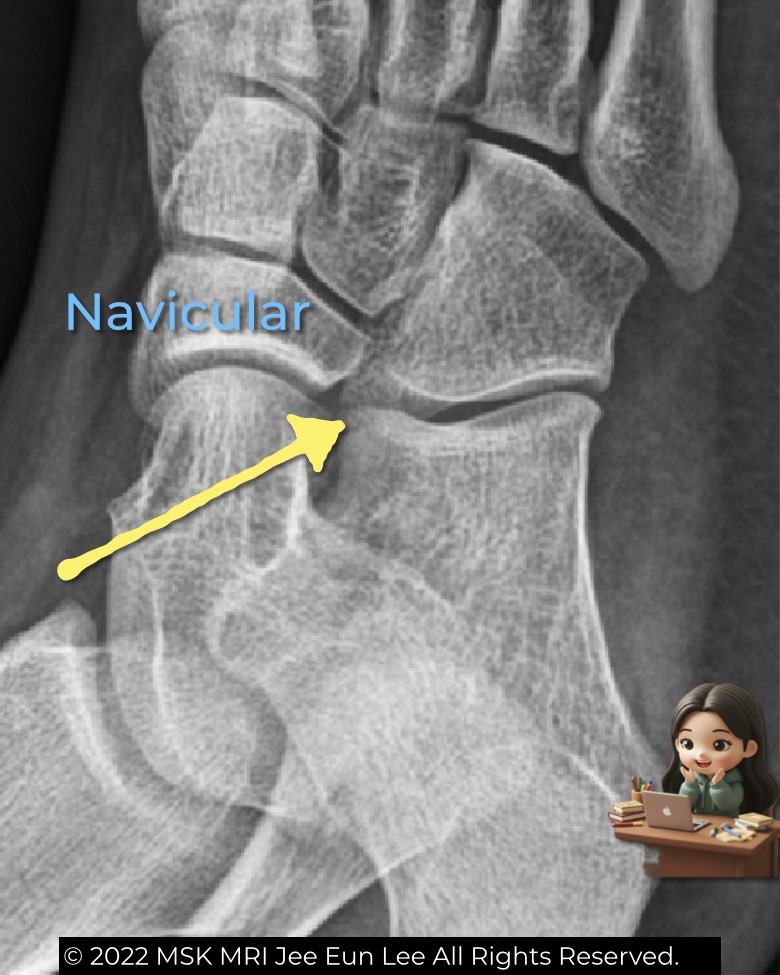

- Oblique view: best for the calcaneonavicular space. Normally, the anterior process of the calcaneus is short, triangular, and separated from the navicular. If it elongates and approaches the navicular, think coalition (Anteater sign).

These simple views provide quick radiographic clues before moving to CT or MRI for confirmation.